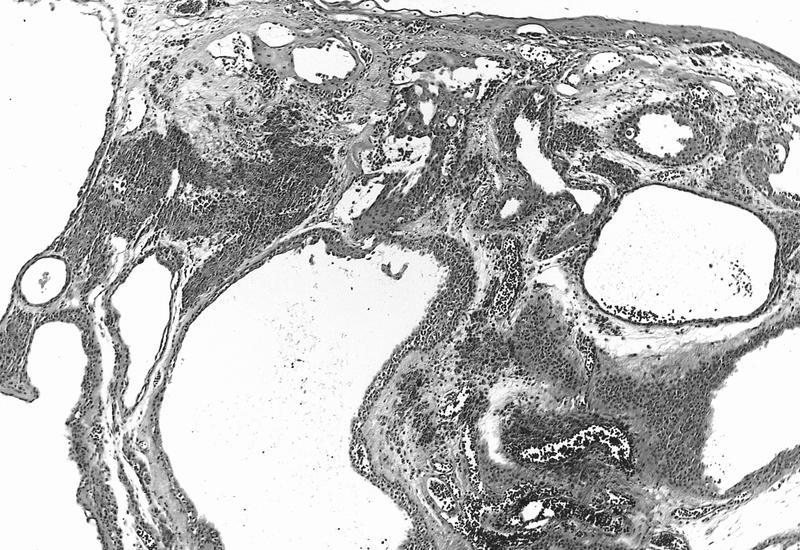

- May have clear cytoplasm due to lipid and central round nucleus (balloon cell nevus)

Balloon cell: